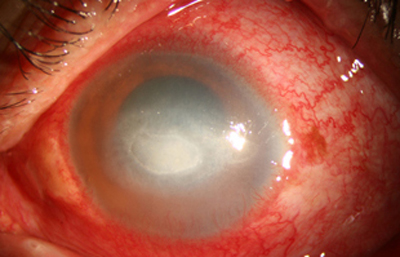

En su evolución se observará aumento del edema, agrandamiento y coalescencia de los infiltrados formando un anillo, (Figura 9, 10 y 11) que progresa hacia la formación de un absceso (Figura 12, 13 y 14), queratolisis superficial, adelgazamiento y perforación corneal (Figura 15 y 16).

La vascularización y el hipopion son poco frecuentes en los estadios tempranos de la queratitis. Con el tiempo, en los estados avanzados de invasión estromal, aparecen vasos estromales (Figura 17)

En los estados avanzados con abscesificación y queratolisis, se enmascara el cuadro corneal, ocultando las características clínicas típicas de la queratitis por Acanthamoeba. (Fig 18)